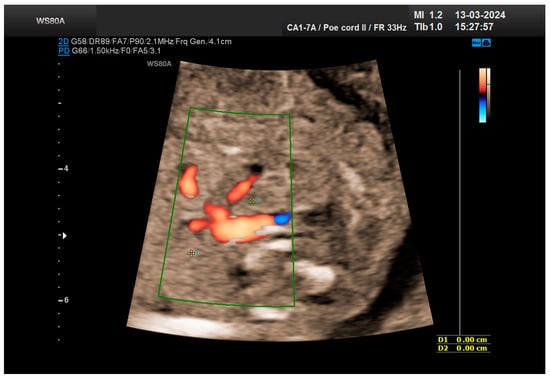

The patient returned at a gestational age of 22 weeks for a second-trimester ultrasound screening. During this examination, the suspicion of crossed fused renal ectopia was confirmed. Axial sections revealed a normal kidney image in the left lumbar fossa and another one, anterior to the spine, without reaching the right renal fossa, fused with the normal left kidney (Figure 5). Two sources of arterial vascularization could be identified, both of them with origins in aorta as follows: one correctly originating from the lumbar aorta, serving the normally positioned left kidney, and another appearing to originate on the anterior border of aorta, at the same level, supplying the ectopic right renal tissue mass (Figure 4 and Figure 6). The bladder was present, with normal appearance and volume. No left ureterohydronephrosis was detected. The presence and course of the right ureter could not be identified. The amniotic fluid volume was normal. No other severe or minor anomalies were observed.

Figure 4. The vascularization of the “renal mass” seems to originate in the aorta. Green box—color Doppler window.

Figure 6. The two kidneys fused with aortic arterial vascularization. Green box—color Doppler window.